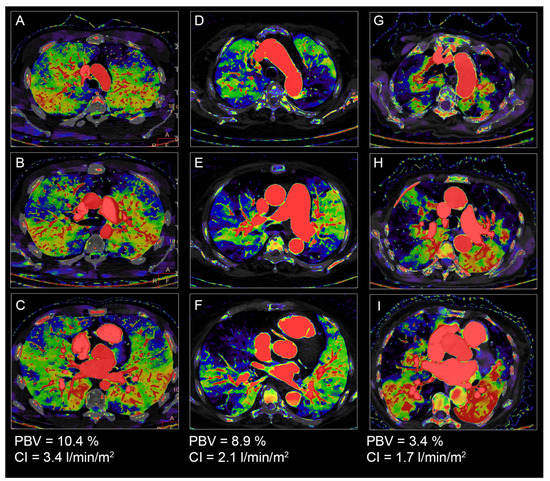

3.3. Diagnostic Performances of Quantitative PBV for Cardiac Index Groups